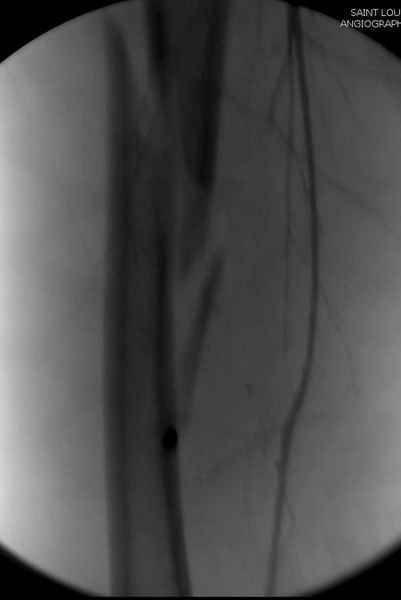

Второй случай тоже репозиция из малого доступа, больному 19 лет, множественные огнестрельные повреждениия конечностей, живота и черепа, правая конечность холодная, без пульсации. Ортопедический диагноз: огнестрельный перелом правого бедра. При срочной ангиографии повреждения сосудов не подтвердилось, конечность из-за ургентности состояния больного зафиксирована временным наружным фиксатором и больной оставлен на операционном столе для срочной лапаротомии хирургической службой.

Больной долго оставался нестабильным, только на 14 день удалось заменить на антеградный интромедуллярный штифт TFN (trochanteric femoral nail) SmithNephew. После неудачной попытки закрытой репозиции, несмотря на использование "joystick", проксимальный стержень от

наружного фиксатора, (перелом начал срастаться) репозицию провели из малого доступа, затем остальные этапы операции.

Случай был представлен из-за того, что больного оперировали после наружной фиксации и был риск инфекцирования через места проведения стержней (на снимках), прошло больше 3 месяцев, выписан из амбулаторной службы из-за отсутсвия надобности дальнейшего наблюдения.